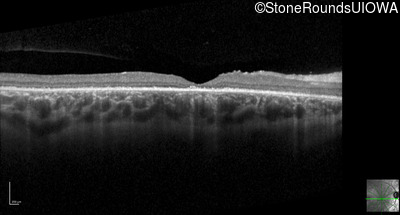

Optical Coherence Tomography - Left - 20/125 -1 sc

Exemplar / OCT Stack

OCT Stack